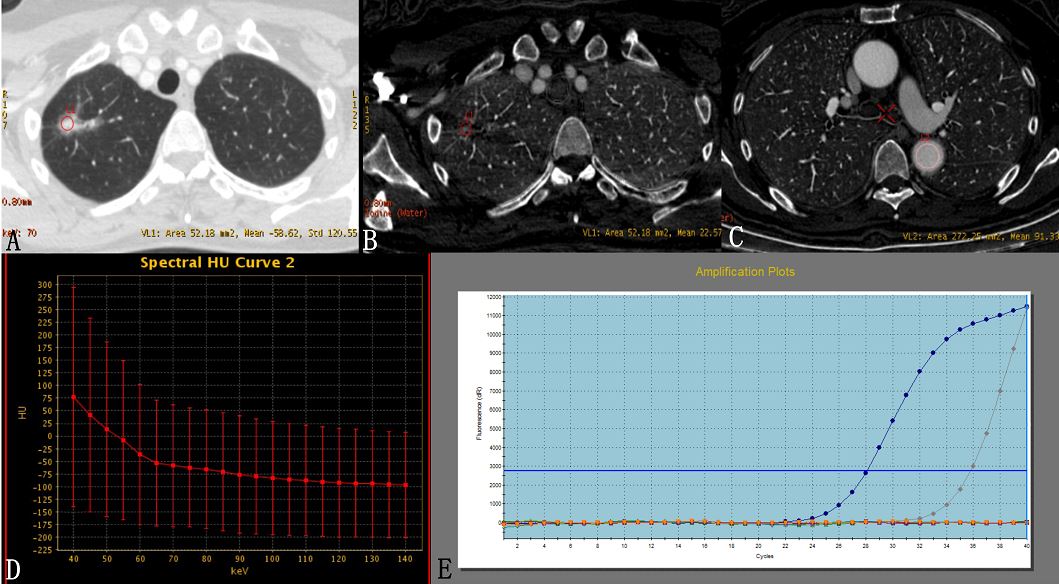

Article: Identification of epidermal growth factor receptor mutations in pulmonary adenocarcinoma using dual-energy spectral computed tomography

Authors: Meng Li, Li Zhang, Wei Tang, Yu-Jing Jin, Lin-Lin Qi, Ning Wu